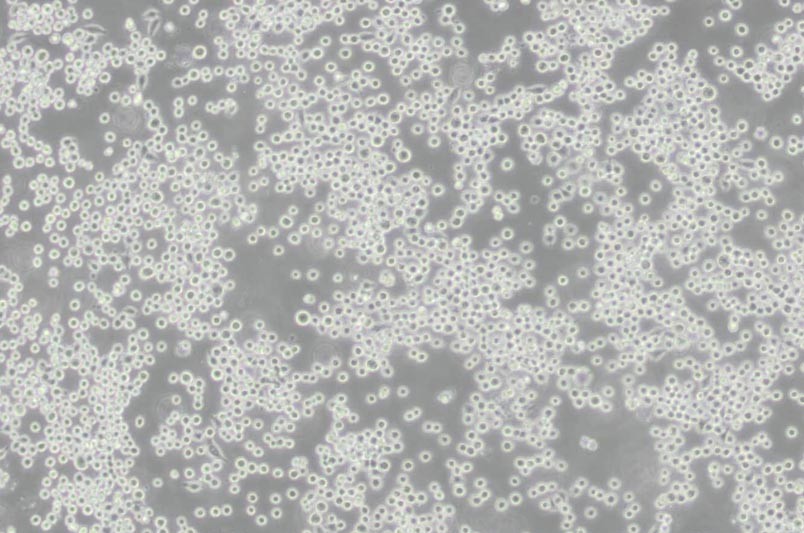

COLO-205人結腸癌細胞

細胞形態 :上皮細胞樣

生長特性 :半貼半懸